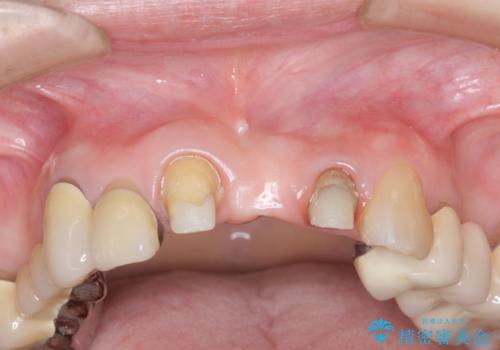

- 前歯の審美障害、見た目の改善を希望され来院されました。

歯肉縁下カリエスも認められるため、挺出を行いセラミックブリッジを審美的に新製します。

挺出について

虫歯が深くなった場合、挺出や歯周外科を行い歯周組織の状態を改善することでより安定した状態で予知性の高いセラミックブリッジを製作することが可能となります。